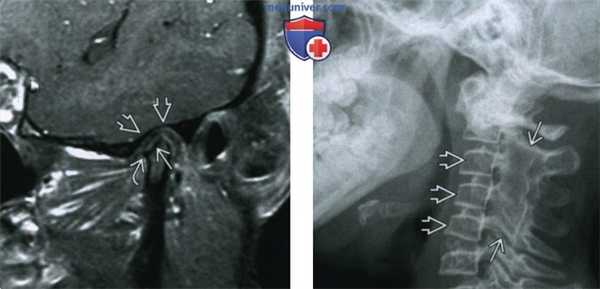

(Справа) При МРТ Т1ВИ FS с КУ b корональной проекции у этой же девочки с ЮИА определяется выраженное контрастное усиление пораженного сустава, а также костного мозга правого мыщелка нижней челюсти, обусловленное его воспалением. Со стороны левого ВНЧС не определяется воспалительных изменений, мыщелок и суставная ямка не выглядят патологически измененными. (Слева) При МРТ Т1ВИ FS с КУ в кососагиттальной проекции у пациентки 21 года с ювенильным идиопатическим артритом определяется уменьшенный мыщелок нижней челюсти с деформированными склерозированными краями с низкой интенсивноаью сигнала. Суставная ямка плоская и расширенная. Контрааное усиление, обусловленное воспалением, отсутствует. Отмечается небольшой остеофит в передних отделах (признак вторичного остеоартроза).

(Справа) На рентгенограмме в боковой проекции у девочки 13 лет, страдающей ювенильным идиопатическим артритом, определяются «классические» изменения: слияние задних отделов С2-С5 и уменьшение передне-заднего размера их тел.

(Слева) При МРТ Т1ВИ FS с КУ в кососагиттальной проекции у пациентки 21 года с ювенильным идиопатическим артритом определяется уменьшенный мыщелок нижней челюсти с деформированными склерозированными краями с низкой интенсивноаью сигнала. Суставная ямка плоская и расширенная. Контрааное усиление, обусловленное воспалением, отсутствует. Отмечается небольшой остеофит в передних отделах (признак вторичного остеоартроза).